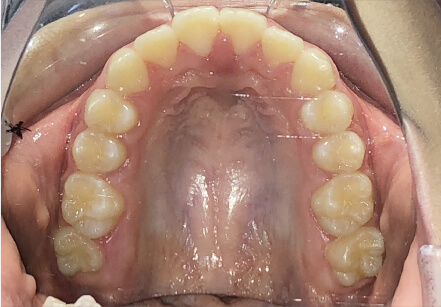

叢生の症例

10歳

/

女性

相談内容

スペース不足

カウンセリング・診断結果

myoからの移行。スペース不足のためインビザライン開始。

治療内容・方法

全額アライナー矯正

術後の経過・現在の様子

クリアライナー使用

治療のリスク

痛み・歯根吸収・歯肉退縮・虫歯・後戻り

費用・治療期間

(インビザのみ)385,000円、1年2ヶ月 + myo3年4ヶ月